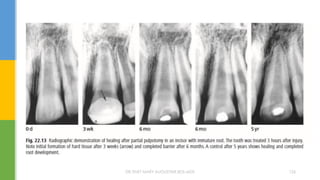

 LUNDY AND STANLEY (1969):Speed of bacterial

INVOLVING DENTIN